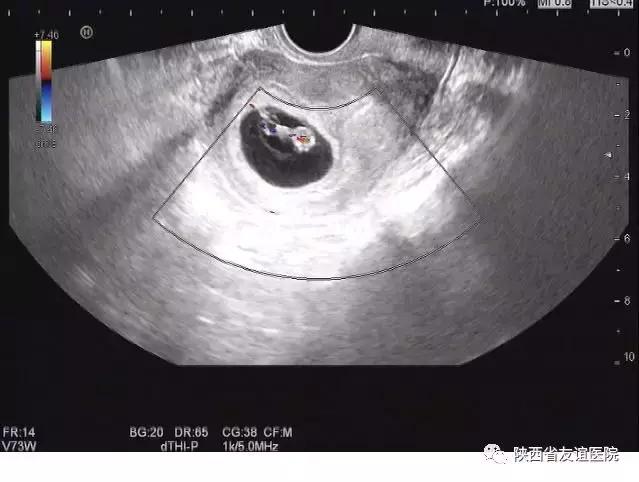

早孕B超图

那么,如果在孕早期6周左右就能按时进行B超检查,这样的事故或者遗憾是不是将会大大减少呢?答案是肯定的。因此,我们还是建议孕早期6周左右需要进行一次有效的B超检查。